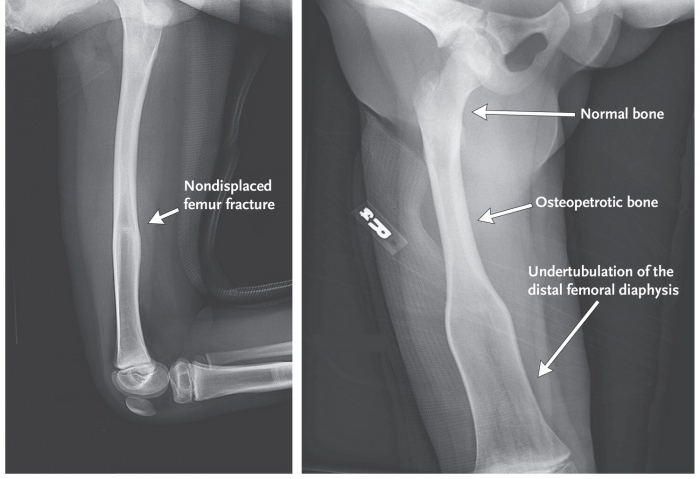

- Рентгеновское исследование. Является одним из самых достоверных способов в данном случае. При этом на снимках можно заметить изменения в структуре. Канал, в котором находится костный мозг, не визуализируется.